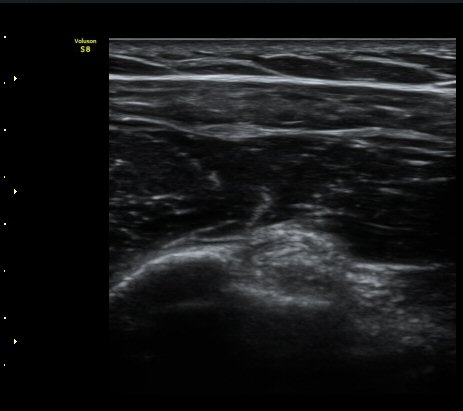

ÀÌµÎ¹Ú±Ù°Ç È¾´Ü¸é°Ë»ç¿¡¼­ ƯÀÌ ¼Ò°ß ¾øÀ½

(no specific abnormal findngs with transverse scan of biceps tendon) »çÁø 1, 2